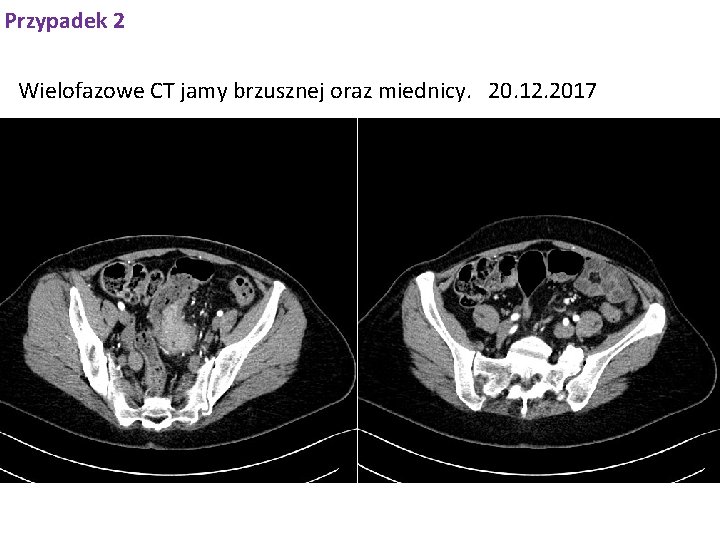

Przypadek 2 Wielofazowe CT jamy brzusznej oraz miednicy. 20. 12. 2017

Przypadek 2 Wielofazowe CT jamy brzusznej oraz miednicy 20. 12. 2017 W dystalnym odcinku esicy widoczny jest okrężny naciek guzowaty o długości ok. 70 mm, zwężający światło jelita (jelito grube powyżej nie poszerzone); naciek przekracza ścianę esicy i obejmuje okoliczną tkankę tłuszczową; na odcinku ok. 25 mm guz przylega do trzonu macicy, natomiast na odcinku ok. 19 mm przylega do górnej ściany pęcherza moczowego. W obrębie krezki esicy widoczne w. chłonne w osi krótkiej do 7 mm. Wątroba niepowiększona, jednorodna; w segm. 2 zmiana o charakterze torbieli o wym. poprz. 23 x 17 mm; poza tym bez zmian ogniskowych. Drogi żółciowe wewnątrzwątrobowe i PŻW- nieposzerzone. Pęcherzyk żółciowy cienkościenny, przeciętnej wielkości. W lewym nadnerczu zmiana ogniskowa o wym. poprz. 25 x 24 mm, bogatotłuszczowa prawdopodobnie gruczolak. Nadnercze prawe typowego kształtu, wielkości, bez zmian ogniskowych. Trzustka niepowiększona, bez zmian ogniskowych. Przewód trzustkowy nieposzerzony. Obie nerki w położeniu typowym, prawidłowej wielkości bez zmian ogniskowych, UKM- y bez zastoju. Śledziona niepowiększona. Naczynia duże jamy brzusznej w normie. Pęcherz moczowy cienkościenny, bez zmian. Struktury kostne objęte badaniem bez zmian destrukcyjnych.